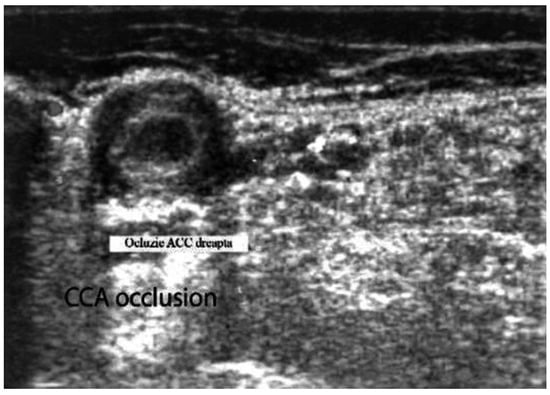

- Acute occlusions, wherein the US image is similar to that of acute embolism in different other vessels, with lack of color Doppler signals (even with low pulse repetition frequency and high color gain) in a visible artery lumen filled with hypoechoic material (cloth) [30,31,32,33,34,35,36,37,38,39,40,41].